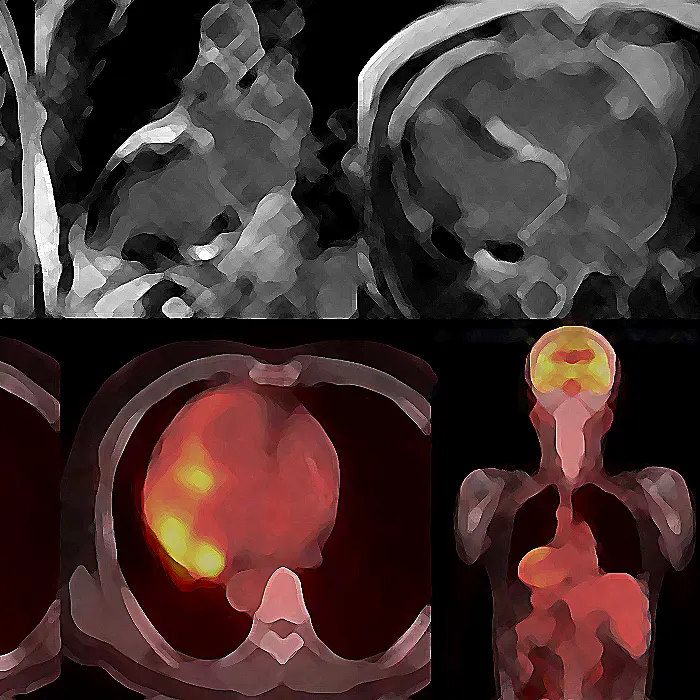

건강검진 흉부 엑스레이 검사나 눈, 피부 등 다른 장기의 증상 등으로 유육종증이 의심되는 경우 추가적인 엑스레이 검사, 갈륨 신티그래피, FDG-PET 검사, 혈액 검사 등을 통해 특징적인 소견이 있는지 확인합니다.기관지경으로 폐포를 세척한 액체를 채취하여 액체의 세포와 성분을 검사하는 검사를 시행하기도 합니다.

특히 주의해야 할 것은 심장에 병변이 있는 유육종증이다. 부정맥, 심부전 등 생명을 위협하는 질환으로 이어질 수 있기 때문에 순환기내과에서 심전도 검사, 심초음파, 조영제 MRI, FDG-PET 검사 등 심장에 대한 정밀 검사를 시행한 후 약물치료, 심박조율기, 심근절제술 등의 치료를 하기도 합니다.